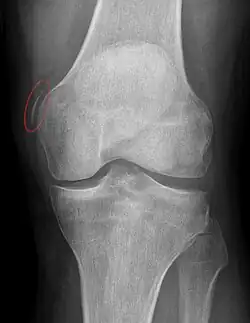

| Pellegrini-Stieda syndrome. Also visible is a fracture of the patella. |

Pellegrini–Stieda syndrome (also called Stieda disease and Köhler–Pellegrini–Stieda disease) is the ossification of the superior part of the medial collateral ligament of the knee. It is a common incidental finding on knee radiographs. It is named for the Italian surgeon A. Pellegrini (b. 1877) and the German surgeon A. Stieda (1869–1945).[1] While the eponym refers to Pellegrini and Stieda, the condition was first discovered by Köhler in 1903, before any namesakes. Pellegrini-Stieda combines the aforementioned radiographic findings and concomitant medial knee joint pain or restricted range of motion.[2]

Diagnosis is typically made on radiographs demonstrating the Pellegrini-Stieda syndrome sign accompanied by pain or restriction of range-of-motion of the knee joint.[2] Pellegrini-Stieda syndrome sign is typically described by a longitudinally linear opacity, which is a process that is describes characteristic of calcification in the soft tissue located medial to the medial femoral condyle.[2] This calcification seen on imaging represents the ossification of the medial collateral ligament, which typically does not develop until approximately three weeks after the initial injury.[2]It is important to note to distinguish this radiographic finding from that of a medial femoral condyle avulsion fracture, which is an injury in which a pulling force of a tendon or ligament fractures away a piece of the bone from its attachment site.[2]